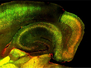

Brain Dance

Your brain starts off as a tube early in development — a neural tube formed from a flat sheet of cells. When the tube doesn't close properly, defects occur that can cause infant death. Exencephaly is the most common defect in neural tube closure. Researchers now investigate neural tube closure using mice, specifically looking at those with mutations in genes encoding a signalling pathway that’s important in brain development, the Sonic hedgehog pathway. They focused on mutations that affected cells at the edges of the flat sheet that becomes the neural tube, revealing that these mice ultimately develop exencephaly. A closer look uncovered that the affected cells didn’t constrict at their tops as they should. This disrupted folding of the flat sheet of neural tissue, as captured using fluorescence microscopy of a mutant developing brain (right) compared to a normal one (left), which provides clues to the genetic and mechanical causes of exencephaly.